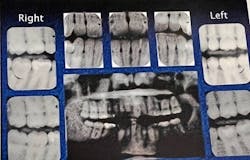

Radiography examination: Panorex and seven vertical bitewings were taken. The radiographs revealed moderate generalized horizontal bone loss on the anterior and posterior teeth. The crestal bone was absent on all teeth, and furcation involvement was noted on tooth no. 30.

Soft-tissue status: Complete six-point periodontal charting was performed with localized 4 mm pockets being noted throughout the patient’s mouth. No recession was detected. However, localized bleeding was evident upon stimulation, and class II furcation was noted on the buccal of no. 30.